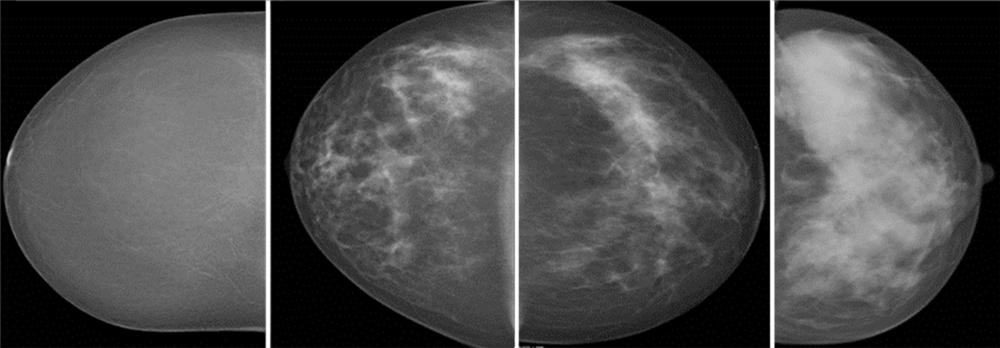

Figure 2. Mammograms show volumetric breast density classified as Volpara density grade 1, 2, 3, and 4 with automated volumetric breast density measurement.